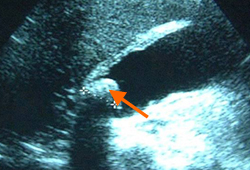

Gravidez ectópica: imagem de ultrassonografia de gravidez ectópica mostrando o sinal de "donut"

Do acervo pessoal de Dra. Melissa Fries, Washington Hospital Center; usado com permissão